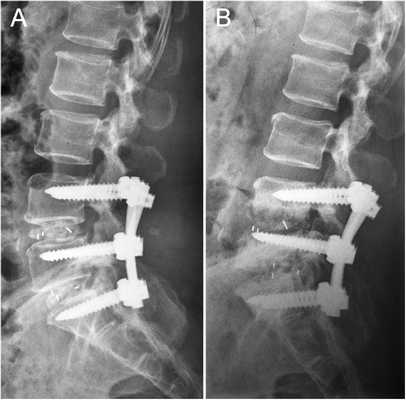

Стабилизационная система на рентгене.

В большинстве случаев проблемный сегмент стабилизируют с помощью металлоконструкций, чаще представленных транспедикулярными системами и пластинами с винтами из высокотехнологичных сплавов металла. В хирургии такая техника называется инструментацией позвоночника. Кроме металлоконструкций, для стабилизации также могут быть применены полимерные устройства, сделанные, например, из углеводородного волокна или резорбирующегося высокомолекулярного биополимера. К отдельной разновидности стабилизирующих вмешательств, которые не причисляют к инструментации, относят установку кейджей имплантатов межпозвоночных дисков.

Кейджы межпозвоночных дисков поясничного отдела.